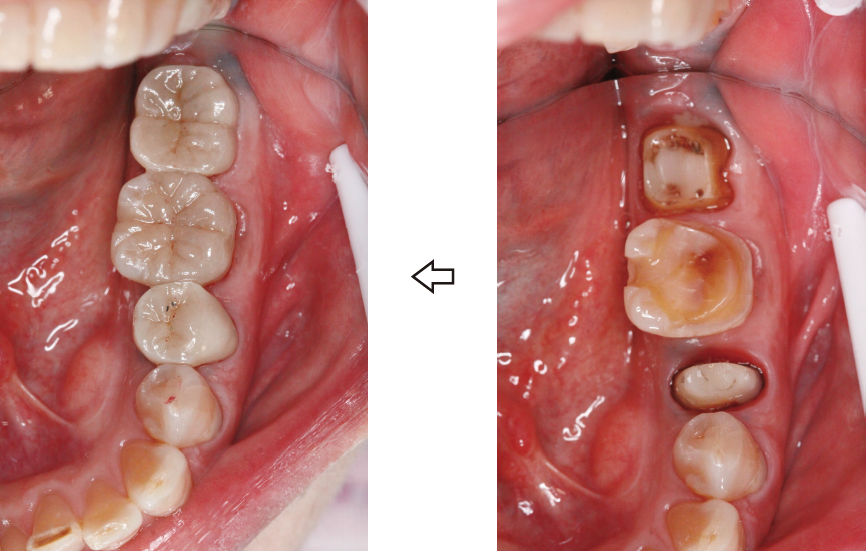

4ヶ月の後、歯がしっかり骨の中に根付いて安定してきたら、次は『仮歯』です。仮歯は本歯に移る前の大事なステップで少しずつ噛ませていく『リハビリ』の段階に入ります。当然他の歯と同じ様にしっかり力強く噛ませるわけではなく弱い力で慣れていく、と言った感じになります。このリハビリは足の骨折のそれと同じ様に『使うことによって回復が促される』と言った効果もあるのでとても大切なステップになります。

この治療を経て、再植終了から6ヶ月程で問題ないと判断したら最終的な本歯になります。(写真4)